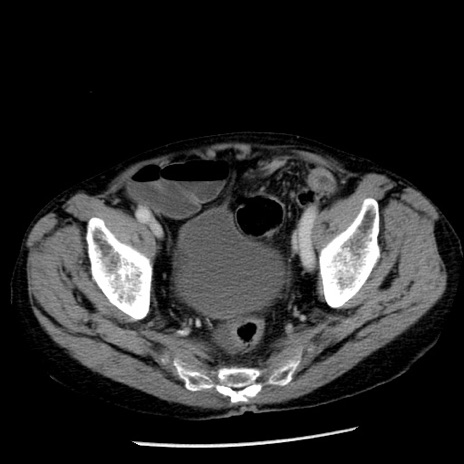

冠状断像

【症例】80歳代男性

【主訴】嘔吐

【現病歴】昨晩2回嘔吐あり、今朝になっても嘔吐あり。来院。

【既往歴】胃潰瘍

【身体所見】意識清明、BT 37.6℃、BP 166/95mmHg、HR 100bpm、SpO2 97%、腹部:平坦・軟、腸蠕動音聴取良好、圧痛なし。

【データ】WBC 21900、CRP 1.46